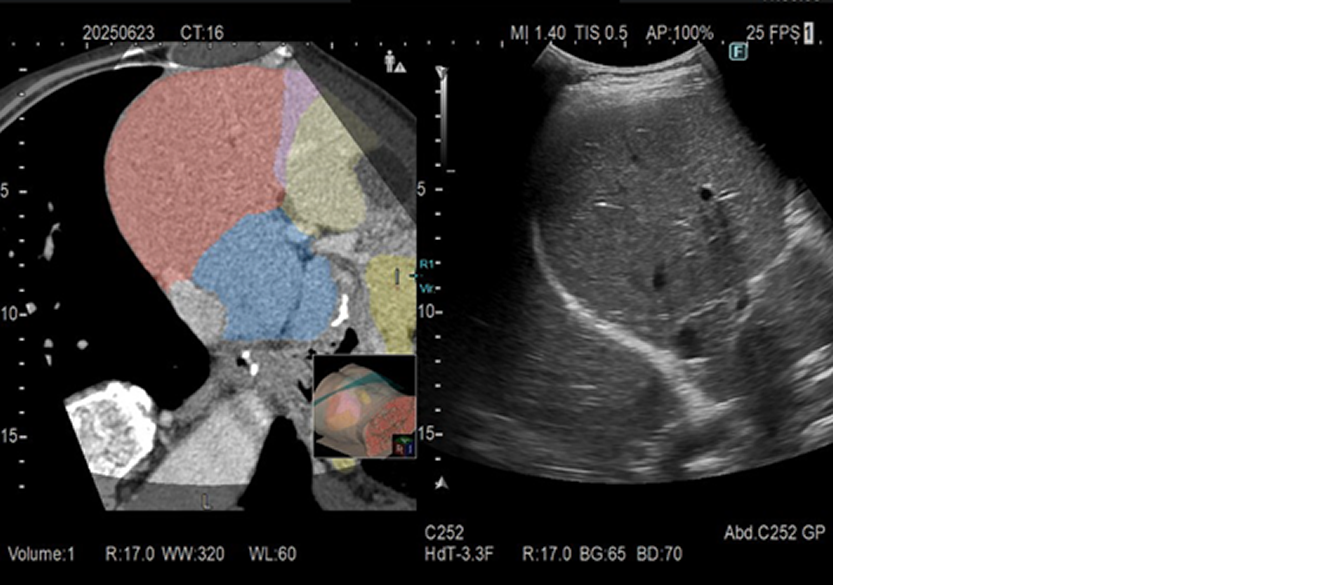

また、CT/MR画像などのバーチャル像の情報から領域を分類して超音波(US)画像に重ねて表示することが可能です。これにより、描出部位の位置関係をわかりやすく可視化し、検査をスムーズに進めるとともに、ワークフローの効率化によって検査時間の短縮が期待されます。

RVSは、超音波画像と他モダリティ画像をリアルタイムに並列表示する機能です。超音波検査だけでは発見しづらい小さな病変の発見や、治療部位の決定など安全かつ正確な治療への貢献が期待されます。「ARIETTA 850 DeepInsight x」「ARIETTA 750 DeepInsight x」は、RVSによる検査開始時のボリュームデータ検索や、バーチャル像と超音波画像との位置合わせを自動化し、操作手順を低減しました。検査者の習熟度を問わず簡単に使用することが可能で、検査の短時間化も期待できます。